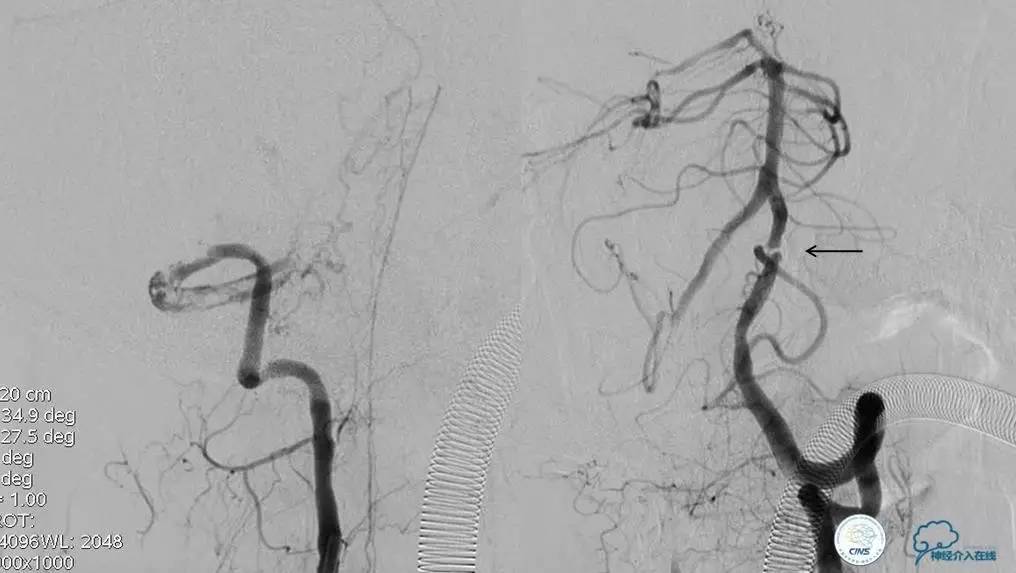

▼开通

出院情况:头晕症状消失,构音障碍缓解,进食无呛咳,饮水实验(-),右侧肢体远端肌力恢复到Ⅰ级。

▼入院MR

神经内科保守治疗。

入院第三天,病情转差。

查体:构音障碍加重,右侧肢体肌力下降(近端Ⅱ级,远端0级)。